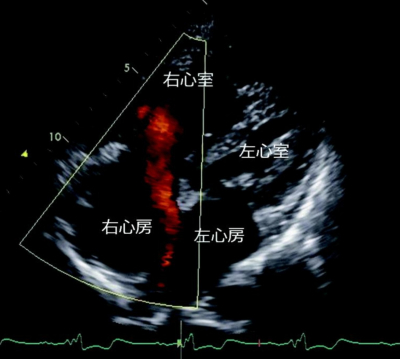

心音はII音の固定性分裂を認め、胸骨左縁第2肋間に収縮期雑音を聴取する。呼吸音に異常を認めなぃ。下肢に浮腫を認めない。手指にチアノーゼ、ばち指を認めない。心電図は洞調律で不完全右脚ブロックを認める。胸部エックス線写真及び心エコー図を別に示す。その後心臓カテーテル検査を行った。

この患者の各部位の酸素飽和度(%)で正しいのはどれか。

(SVC:上大静脈、RA:右心房、RV:右心室、PA:肺動脈、LV:左心室)